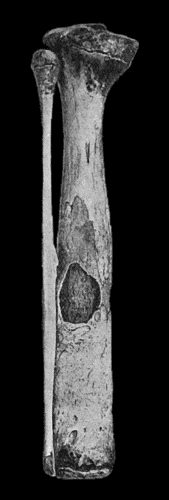

| 118. | Shaft of the Femur after Acute Osteomyelitis | 444 |

| 119. | Femur and Tibia showing results of Acute Osteomyelitis | 445 |